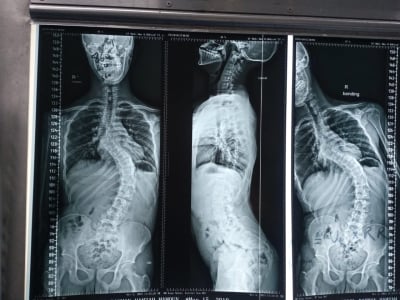

إنجاز طبي في مستشفى الأمير حمزة: تصحيح جنف حاد بالعمود الفقري

الوقائع الإخباري: شهد قسم جراحة العمود الفقري في مستشفى الأمير حمزة إنجازًا طبيًا مميزًا تمثّل في إجراء تدخّل جراحي معقّد لتصحيح جنف العمود الفقري لدى أحد المرضى الذين يعانون من تشوّه حاد في الفقرات.

وقد أُجريت العملية باستخدام جهاز الملاحة الجراحية المتقدّم، الذي أتاح دقةً عالية في التعامل مع التشوّهات البنيوية الشديدة، وسهّل توجيه الأدوات الجراحية ضمن المسار الآمن والمثالي.

كما اشتملت العملية على إزالة أجزاء محددة من الأطراف الخلفية للفقرات لتحقيق التصحيح المطلوب واستعادة التوازن والمحاذاة الطبيعية للعمود الفقري.